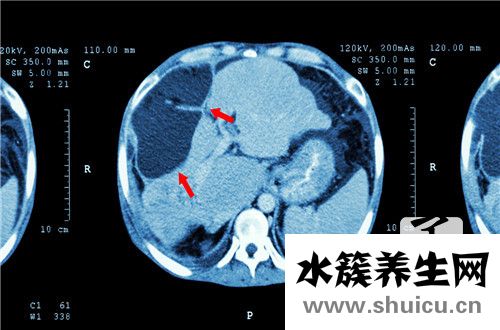

肝功檢查有多種指標(biāo)值,常見的肝功檢查新項(xiàng)目關(guān)鍵包含有:谷丙轉(zhuǎn)氨酶、谷草轉(zhuǎn)氨酶、直接膽紅素、間接膽紅素、總膽紅素,總蛋白、血蛋白、人體白蛋白、γ-谷氨酰轉(zhuǎn)肽酶、堿性磷酸酶、凝血酶原活動(dòng)力等。這種指標(biāo)值可以體現(xiàn)出肝功能檢查是不是一切正常。而且一些指標(biāo)值針對(duì)病況的醫(yī)治擁有 關(guān)鍵的指導(dǎo)作用,因而需要大伙兒有一定的掌握。那麼肝功能異常指標(biāo)值是啥?

1、轉(zhuǎn)氨酶出現(xiàn)異常 當(dāng)肝臟組織損傷時(shí),轉(zhuǎn)氨酶便會(huì)上升,包含谷丙轉(zhuǎn)氨酶和谷草轉(zhuǎn)氨酶。轉(zhuǎn)氨酶本來是在肝臟中的,當(dāng)肝臟損壞的情況下便會(huì)釋放出來到血液中去,因而當(dāng)肝臟組織損傷便會(huì)出現(xiàn)轉(zhuǎn)氨酶升高的狀況。

2、總膽紅素出現(xiàn)異常 總膽紅素可分成立即膽紅和間接膽紅素。假如出現(xiàn)直接膽紅素和間接膽紅素另外上升的狀況,很有可能是肝臟的肝臟對(duì)總膽紅素的攝入、融合或代謝出現(xiàn)了阻礙,應(yīng)該馬上采取有效的醫(yī)治。總膽紅素標(biāo)準(zhǔn)值為1.7~17.1umol/l,直接膽紅素標(biāo)準(zhǔn)值為0.0~3.42 umol/l,,間接膽紅素標(biāo)準(zhǔn)值為1.7~13.68 umol/l。

3. 人體白蛋白和血蛋白 ALB(人體白蛋白)減少,GLB(血蛋白)上升,是肝功能異常的指標(biāo)值,可表明肝臟的貯備工作能力出現(xiàn)了出現(xiàn)異常,需要立即醫(yī)治。ALB(人體白蛋白)標(biāo)準(zhǔn)值為40~55g/L,GLB(血蛋白) 標(biāo)準(zhǔn)值為20~30.0 g/L,A/G(白球比) 標(biāo)準(zhǔn)值為(1.5~2.5):1。

4. γ-谷氨酰轉(zhuǎn)肽酶和堿性磷酸酶 常體現(xiàn)肝代謝作用和膽管代謝作用。γ-谷氨酰轉(zhuǎn)肽酶(γ-GT)和堿性磷酸酶(ALP)上升,應(yīng)考慮到肝臟和膽道系統(tǒng)的損害和發(fā)炎及膽道阻塞。如原發(fā)性膽液性肝硬化、原發(fā)性強(qiáng)制膽管炎、灑精性肝炎或慢性肝炎、膽石癥,壺腹癌和胰腺癌被壓迫膽總管等。

自然,腎臟功能生物化學(xué)檢驗(yàn)結(jié)果是一個(gè)十分復(fù)雜的問題,需要融合病人病況綜合性具體分析,才可以做出較客觀性恰當(dāng)?shù)拇_診。